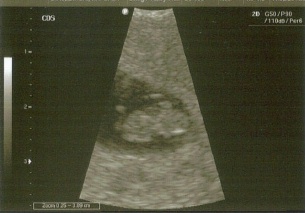

My second ultrasound!

I can actually see my little sea creature on this one! I was released form my RE and I can now see my regular doctor. I am so excited and at the same time still so scared! XOXOXO BOTB